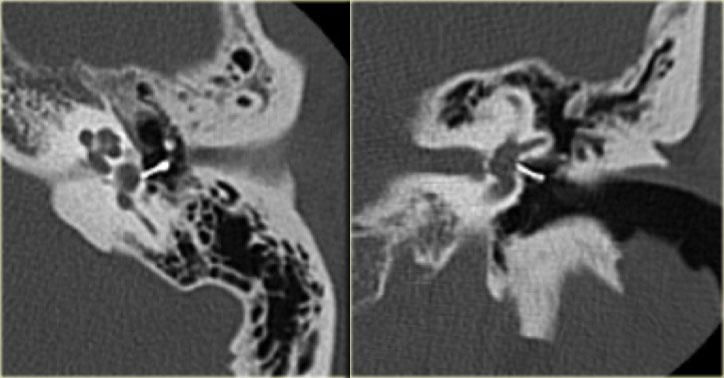

Bên trái là hình ảnh của một bé trai 2 tuổi với teo ống tai ngoài xương hai bên.

Xương búa và xương đe hợp nhất (mũi tên).

Ốc tai bình thường.